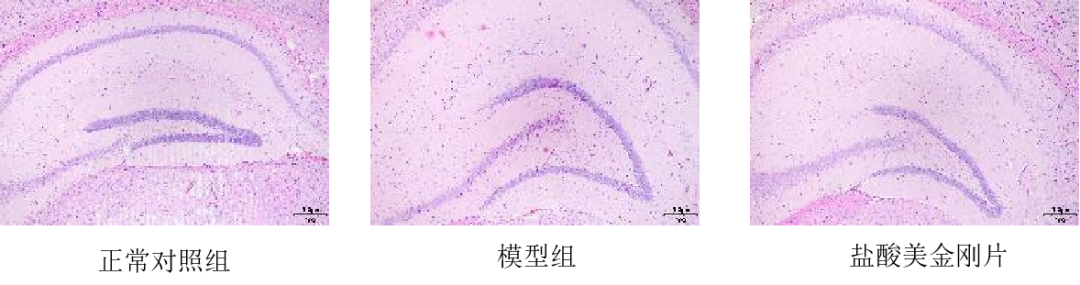

造模方式:转基因小鼠继续饲养4周后进行巴恩斯迷宫和旷场实验行为学检测,检测后进行脑组织的病理检测以及Aβ42和NEP的表达情况。

阳性药:盐酸美金刚片

模型数据